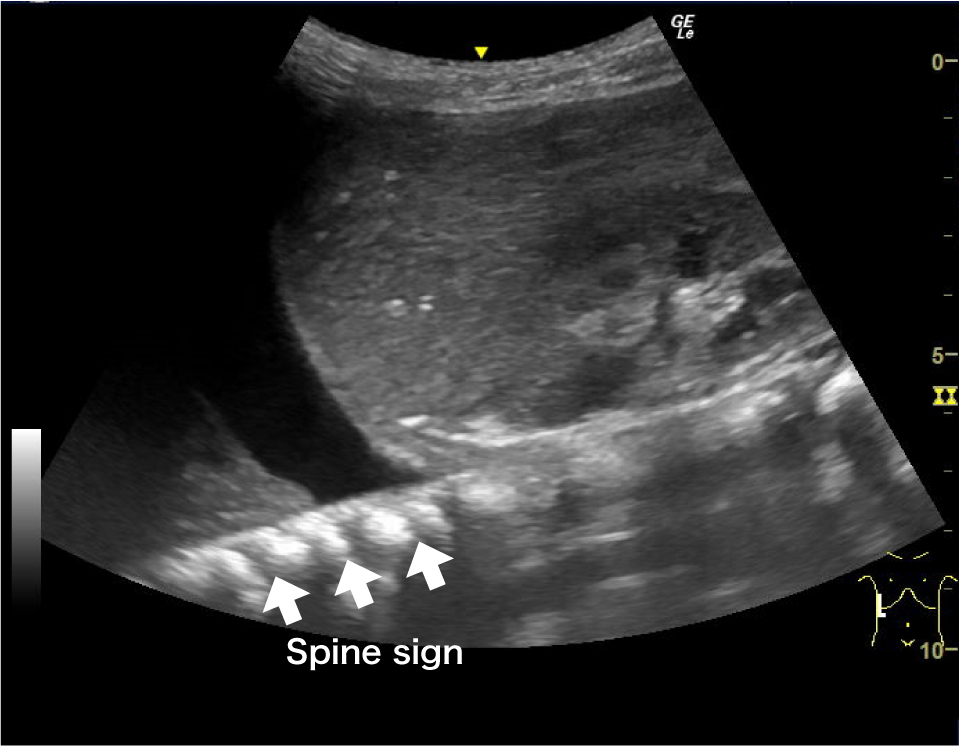

| Spine sign | 腹腔内の実質臓器経由でしか観察できない脊椎が,胸水を介して横隔膜より頭側でも観察できる所見. |

胸腔を観察するにはまず横隔膜,肝臓,脾臓,胸膜を確認するが,胸水が貯留している場合,正常で見られるはずのcurtain signは消失し,胸水は胸腔内の無エコー域として描出される(Fig.11).Mモードで確認できるsinusoid signや,貯留した胸水を通して脊椎が横隔膜より頭側でも描出されるspine sign(Fig.11)も併用して診断できる.

通常脊椎は腹腔内の実質臓器経由でしか観察できないが,胸水貯留があると胸水を介して横隔膜より頭側でも観察できる(→:spine sign).